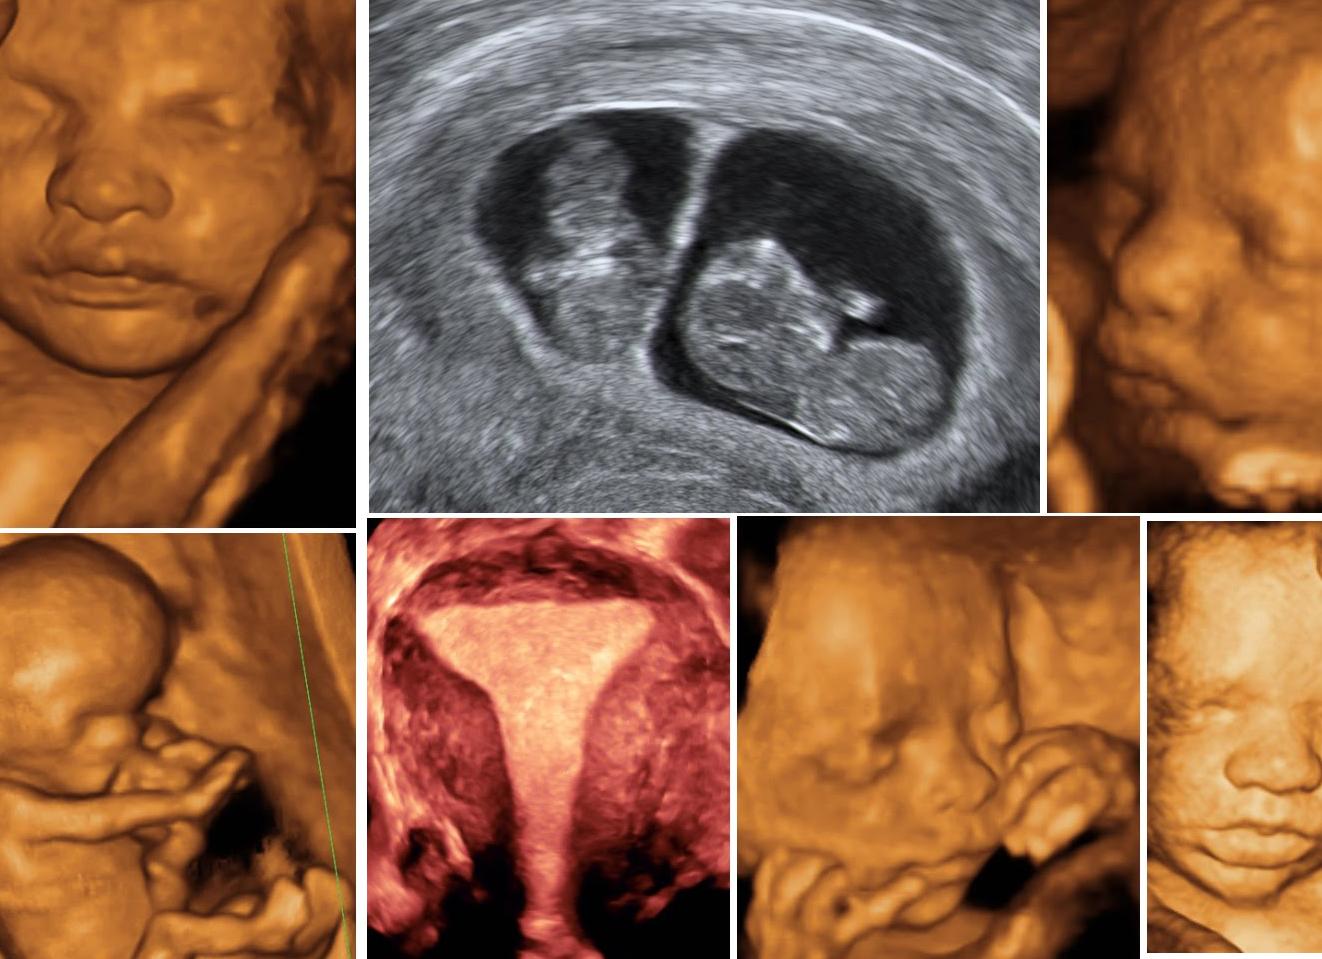

В современном мире беременность женщины с самых ранних сроков проходит под наблюдением врача. При этом назначаются различные анализы и обследования для определения состояния здоровья будущей матери и развивающегося внутри утробы ребенка. Чтобы вовремя обнаружить возможные нарушения при формировании и развитии плода, проводят ультразвуковые исследования, в том числе и допплер. Не все знают, что это такое, насколько безопасно это исследование, что показывает и зачем его выполнять.

При беременности с помощью допплерографии изучают кровоток в сосудах плода, плаценты и матки. Ультразвуковые волны, отражаясь от исследуемых сосудов, изменяют частоту. Эти изменения фиксируются компьютером, обрабатываются и выдаются в приемлемой форме.

Во время беременности образуется третий круг кровообращения, который связывает организм матери и ребенка, делает систему кровотока единой. Доплер УЗИ при беременности (сокращенно УЗДГ) помогает контролировать систему кровообращения, а значит и состояние ребенка, динамику развития, соответствия срока беременности фактическому, а при необходимости оценить эффективность проводимого лечения. Доплерография плода используется для измерения скорости кровотока в сосудах фетоплацентарной и маточно-плацентарной систем в зависимости от фазы сердечного цикла.

В основе исследования — допплерографии, лежит принцип отражения движущимися частицами крови ультразвуковой волны. На экране монитора отражение кровотока регистрируется как красные сполохи-приток, либо синие-отток, а специальная программа делает возможным анализировать отраженную волну и выводить на экран в виде цифровых показателей, характеризующих скорость кровотока в сосудах (венозных и артериальных), так называемая, допплерография.

Допплерометрия плода и допплерография плода подобна обычному УЗИ. Как правило, все современные УЗ-аппараты позволяют проводить и обычное УЗИ, и допплерографическое исследование. При помощи УЗДГ можно визуализировать и оценить кровоток в жизненно важных органах ребенка (особое значение придается изучению кровотока в таких органах, как головной мозг, сердце, печень плода), сосудах плаценты. В отличие от обычного ультразвукового исследования, позволяющего лишь визуализировать органы и ткани, УЗИ с доплером позволяет оценить состояние здоровья плода, выявить серьезные нарушения и гипоксию на самых ранних стадиях, а значит помогает вовремя начать лечебные мероприятия до наступления необратимых явлений, связанных с первоначальными изменениями кровотока в плаценте, пупочных сосудах.